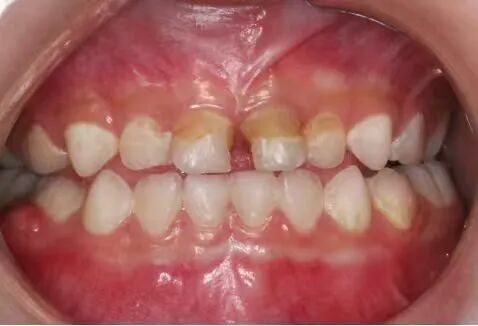

奶瓶喂养的幼儿易患“奶瓶龋”↑ 韩耀伦 供图

龋坏的牙齿↑ 河南省人民医院韩耀伦 供图